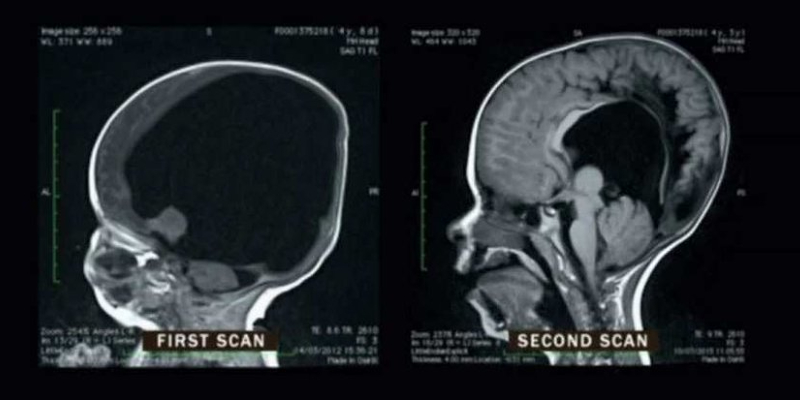

نواه وال ..الصبي الذي ولد دون عقل

ولد نواه وول في عام 2008 بحالة نادرة للغاية تسمى كولبوسيفالي التي تؤثر على تطور…